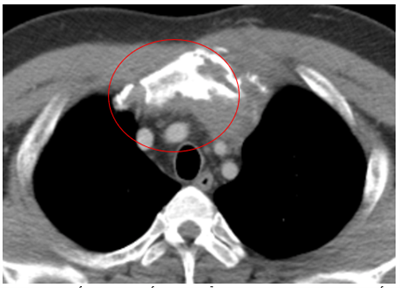

Ca lâm sàng:Hiệu quả điều trị đích bằng Osimertinib ở bệnh nhân UT biểu mô tuyến của phổi giai đoạn IV có đột biến gen EGFR L858R (Exon 21) tại Trung tâm YHHN&UB-Bệnh viện Bạch Mai

Ung thư phổi là một trong những ung thư có tỷ lệ mắc và tử vong cao nhất trên toàn thế giới. Theo GLOBOCAN 2022, ung thư phổi đứng thứ hai về số ca mắc mới với khoảng 2,5 triệu trường hợp mỗi năm và là nguyên nhân hàng đầu gây tử vong do...